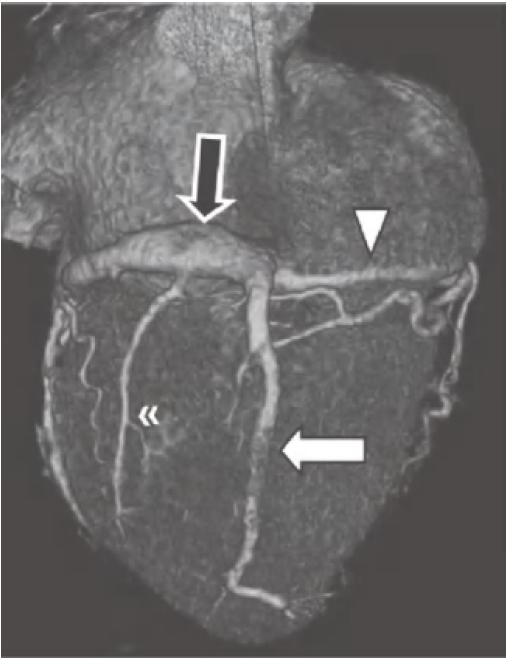

图13-4 RCA优势型,RCA绕过右心缘,在RAVG的下方发出后降支(箭),并走行于后室间沟(虚线)。心中静脉(箭头)也在后室间沟内走行

RCA.右冠状动脉;RV.右心室;LV.左心室

当冠状动脉为RCA优势型时,RCA可走行至RAVG的下部,并发出走行于后室间沟的后降支。在约50%的RCA优势型人群中,还有一条明显的后外侧支,沿LAVG的下半部分走行,供应左心室下外侧壁心肌。这一分支还可能为二尖瓣的下间隔乳头肌供血,因此对其进行准确识别尤为重要。